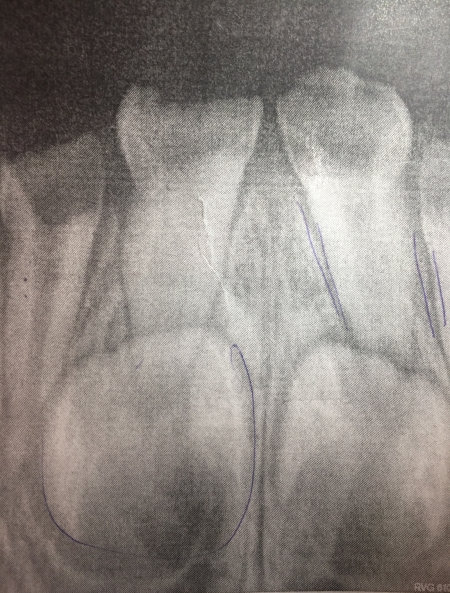

И вот спустя полгода от зубов остались одни пеньки. Сегодня сходили в другую стоматологию предлагают лечить под наркозом. Не дают гарантии, что можно вылечить, сказали, что может, удалят зубы. Сделали снимок, сказали, что есть инфекция возле корня зуба.